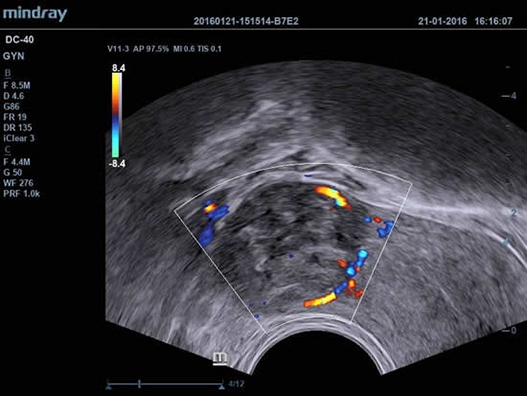

Mindray DC-40 - передовая УЗ-станция с выдающимися возможностями в области медицинской диагностики. Компания Mindray разработала это устройство с учетом высоких требований врачей к качеству изображения и быстродействию. DC-40 обеспечивает высокое качество изображения и точность диагностики, что является необходимым в повседневной практике врачей. Технологии, применяемые в этом устройстве, позволяют получать четкое и детализированное изображение.

Технологии iBeam, iClear и iScape, применяемые в DC-40, позволяют получать объемные изображения высокого качества без помех и зернистости в зоне сигнала. Панорамная визуализация с расширенным обзором анатомических структур решает проблемы сложных диагнозов, которые ранее создавали значительные трудности в ультразвуковой диагностике.

• Shared Service Package - предустановленные параметры, аннотации, маркеры, программы измерений для абдоминальных исследований, акушерства, гинекологии, кардиологии, ангиологии, исследований малых органов, урологии, педиатрии, неотложной медицины;

• Внутриполостной датчик Mindray V11-3